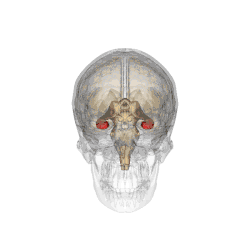

Hipokampus (řec. hippocampus ) je součástí limbického systému. Umístěn je ve střední části spánkového laloku, jeden v pravé a druhý v levé mozkové hemisféře. Je součástí limbického systému a hraje velkou roli při krátkodobém uchovávání informací a při prostorové orientaci. Při Alzheimerově chorobě je hipokampus mezi prvními částmi mozku, která utrpí poškození. Poškození hipokampu může také způsobit nedostatek kyslíku (anoxie), zánět mozkových blan nebo epilepsie střední části spánkového laloku. Lidé se značným poškozením hipokampu trpí poškozením paměti a neschopností ukládat nové informace.